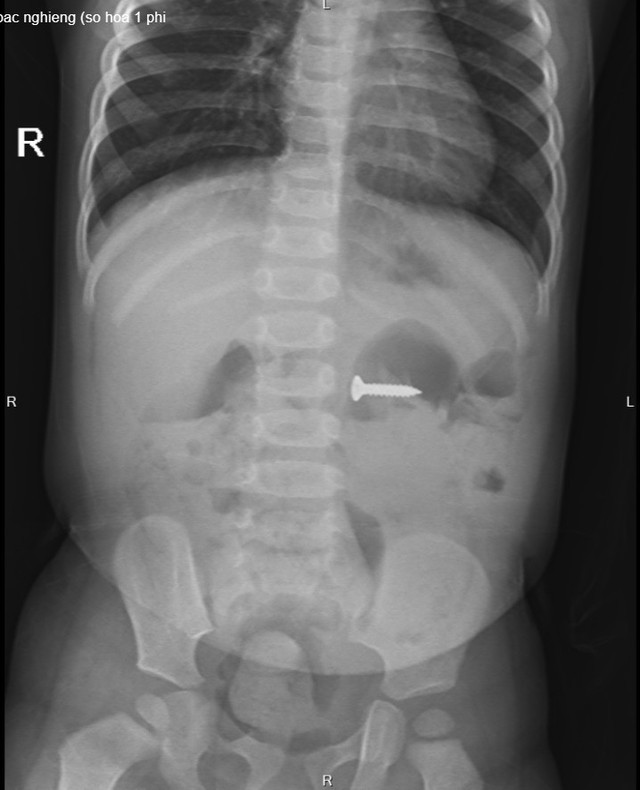

| Bác sĩ thăm khám lại cho bệnh nhi sau khi gắp đinh vít sắc nhọn trong dạ dày của bé |

Hiện tại, bệnh nhi được theo dõi sức khỏe tại Khoa Cấp cứu. Qua trường hợp này, các bác sĩ khuyến cáo, phụ huynh hoặc người trông trẻ cần hết sức chú ý, không nên để các bé chơi các loại đồ vật có kích thước nhỏ bởi với sự hiếu động, tò mò, bé sẽ ngậm vào miệng rồi vô tình nuốt luôn dị vật dẫn đến hậu quả đáng tiếc.